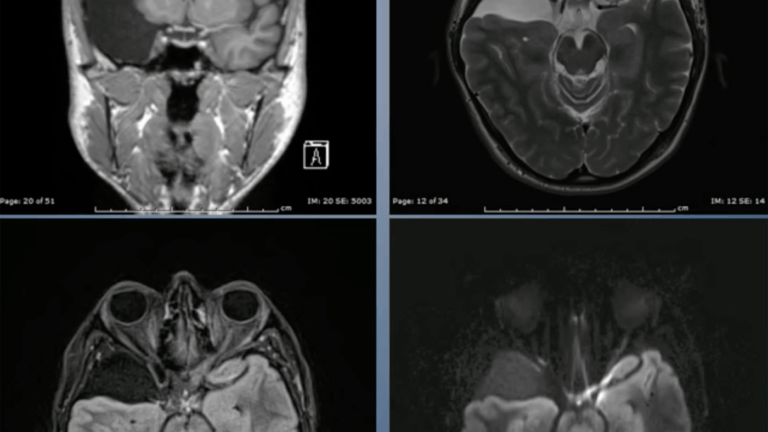

four scans of a brain

Endoscopic Arachnoid Cyst Fenestration